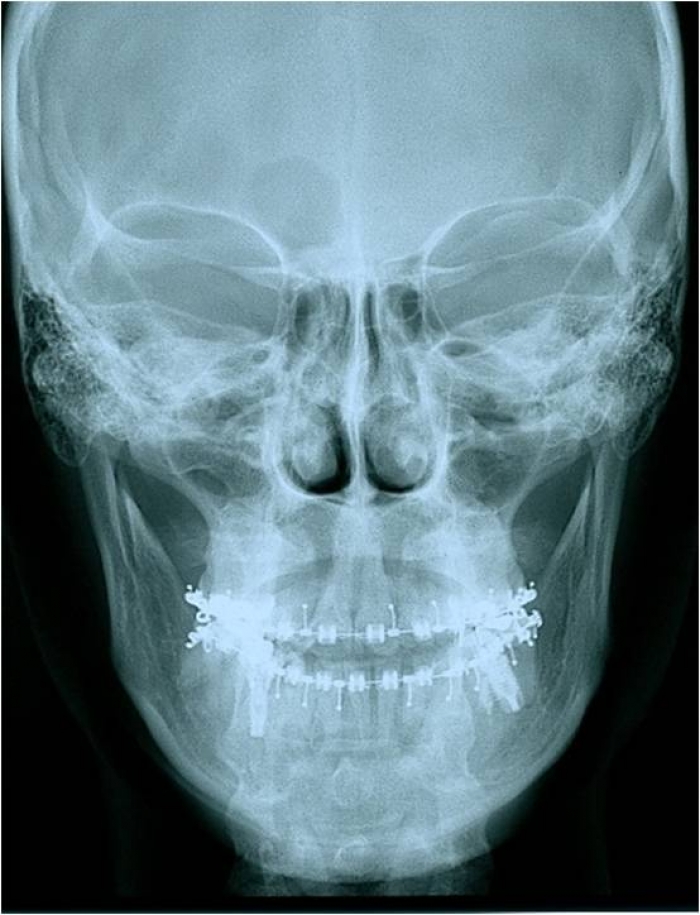

Telerradiografia frontal inicial

Telerradiografia frontal após a cirurgia